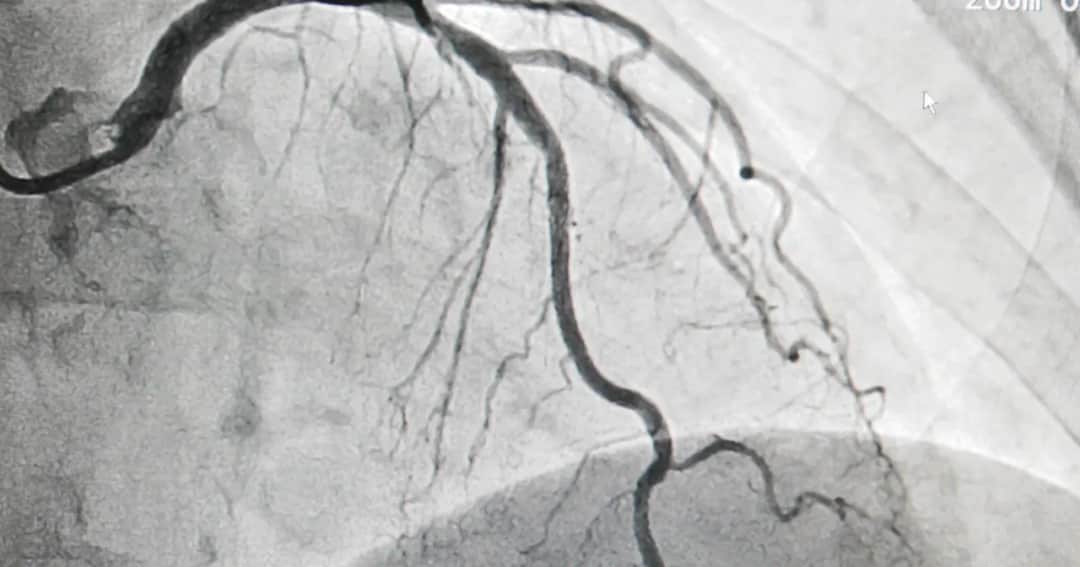

Poznaj, czym jest koronografia, co to za badanie i jak może pomóc w diagnozowaniu chorób serca, poprawiając Twoje zdrowie i jakość życia.